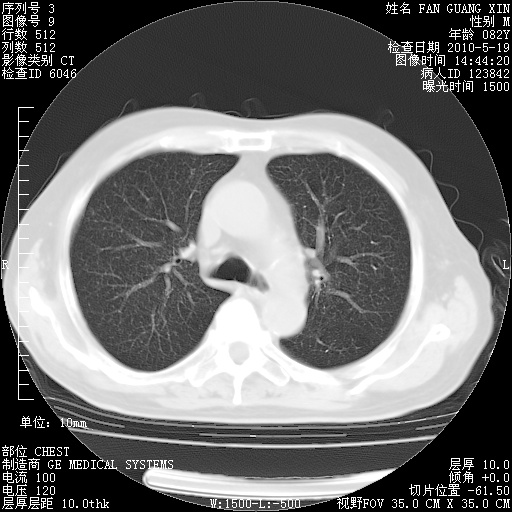

复查肺部CT,明显好转。为什么发热呢?

治疗3周后的肺部CT